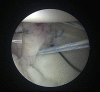

Capsulolabral augmentation is one of the most used arthroscopic techniques to address multidirectional instability of the shoulder. Given the thin and weak capsule seen in the affected patients, reconstruction in this subset of patients can be particularly challenging. This arthroscopic technique aims to reduce the capsular volume and deepen the glenoid socket through the creation of a particularly voluminous "bumper" along the glenoid bone. Increasing the depth of the glenoid facilitates a concavity-compression stabilizing effect and, therefore, shoulder stability, especially midrange stability. This technique aims to augment the bump of the standard capsulolabral reconstruction by using a resorbable surgical mesh derived from porcine skin.